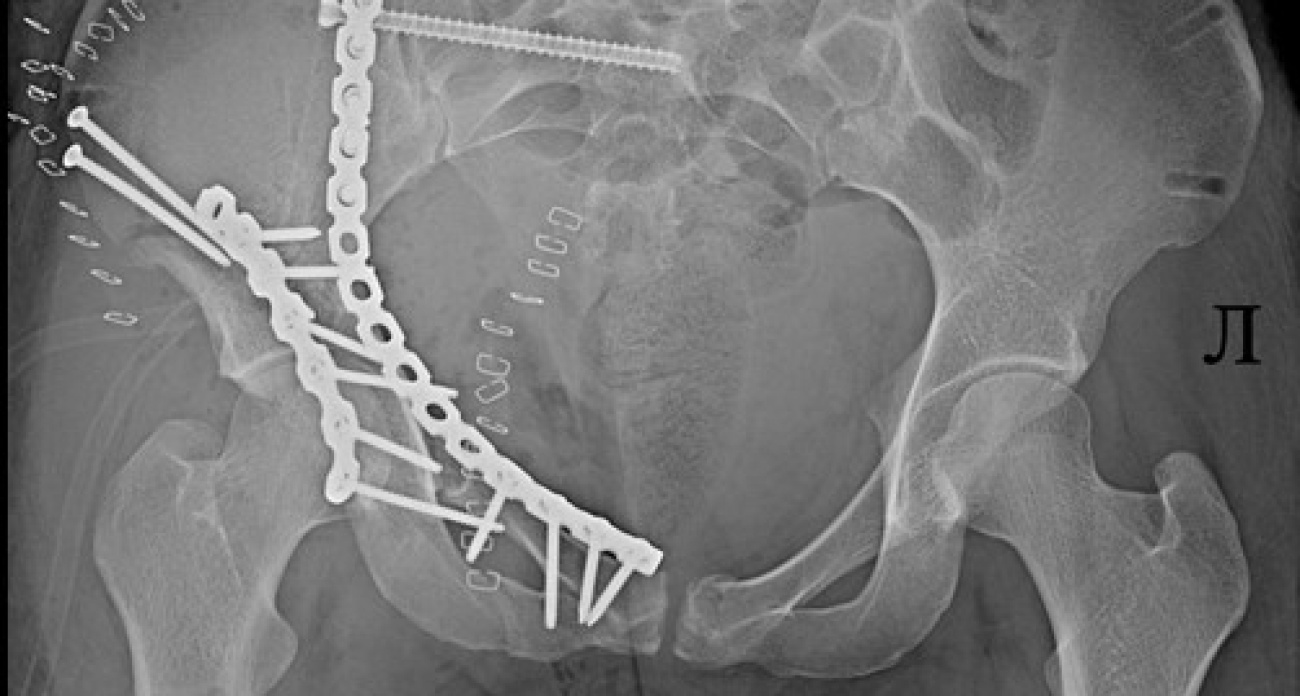

В Ярославле 25-летняя девушка оказалась в реанимации после удара о бетонный блок на стихийной горке. У нее — множественные переломы таза и впереди долгие месяцы реабилитации.

"Лечение таких повреждений чрезвычайно сложное и длительное. Оно включает многоэтапные операции, иногда продолжительностью пять часов, использование наружных фиксаторов и имплантатов, длительный период восстановления",-рассказали в больнице.